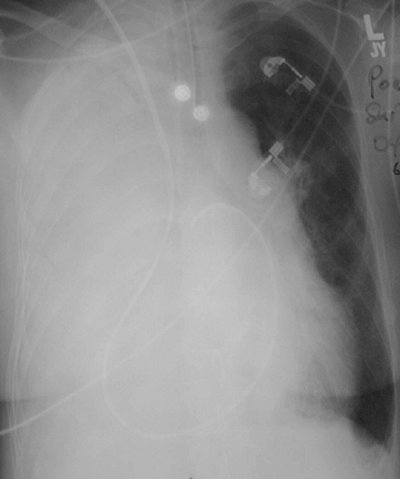

Transvenous Pacemakers

Numerous types of single- and dual-lead pacemakers and combination pacer–defibrillators are available. They are used to treat a variety of dysrhythmias. Accurate interpretation of their appearance on chest radiography requires knowledge of the specific type of pacemaker placed. The three major approaches to insertion of a pacemaker electrode into the heart include epicardial, subxiphoid, and transvenous implantations; transvenous is the most common. With single-lead pacers, the wire is placed into the right ventricle by way of the cephalic, subclavian, or jugular vein. When the lead is wedged into the myocardial trabeculae near the cardiac apex, the lead will be stable and have maximal contact with the endocardial surface. With dual-lead pacers, one lead is generally placed into the right atrium and the other into the right ventricle. It is important to know where the desired placement of leads is for each patient, because placement within the coronary sinus may be accidental or purposeful. After the electrodes are positioned, the generator is placed in a pouch in the subcutaneous tissues of the chest wall or beneath the pectoralis muscle. Biventricular pacemakers are used to treat congestive heart failure. Leads are placed in the right atrium and right ventricle, and a third lead is placed in the coronary sinus for pacing the left ventricle (Fig. 5-18).